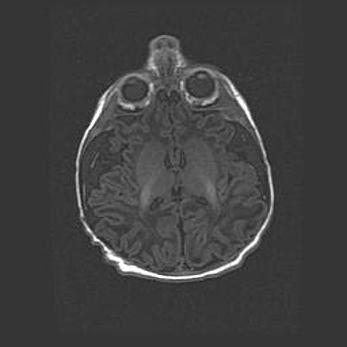

Наружная гидроцефалия с возможной атрофией височных областей.

Возраст: 28 дней

Вес: 3670 г

Пол: мужской

Окружность головы: 38 см

Срок гестации: 40 недель

Гидроцефалия головного мозга у новорожденных – это заболевание, которое характеризуется скоплением избыточного количества спинномозговой жидкости в желудочковой системе головного мозга в результате затруднения её перемещения от места выработки к месту поглощения в кровеносную систему или вследствие нарушения абсорбции. При открытой наружной форме гидроцефалии у новорожденных расширяются и переполняются субарахноидные пространства.

При нормотензивных  формах,  которые,  как  правило,  являются  следствием  перенесенных ишемических  повреждений  паренхимы  мозга,  возможно  сочетание микроцефалии  с нормотензивной гидроцефалией. В основе данных изменений лежит атрофия больших полушарий с преимущественной  локализацией  в  лобно-височных  областях.